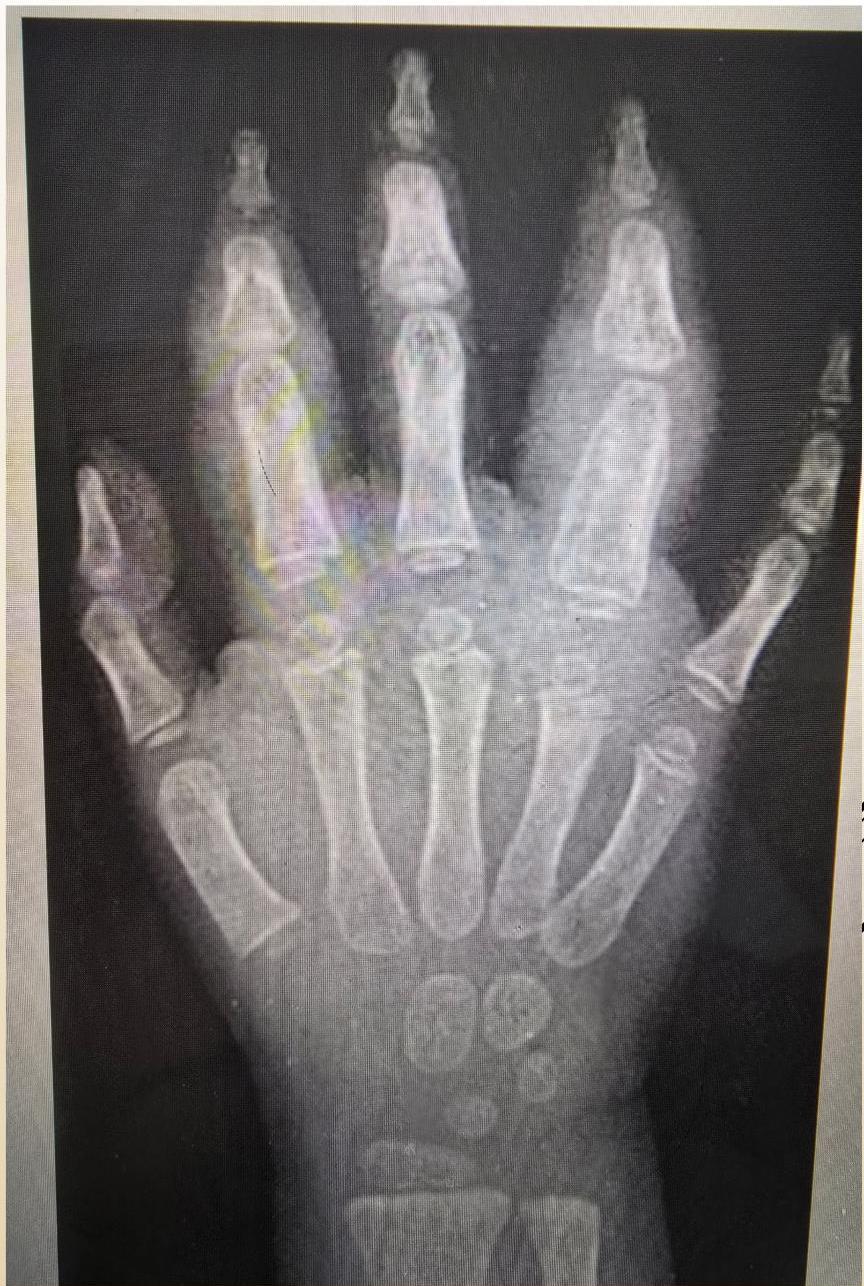

Imaging Findings (sJIA)

Early radiographic changes (6 month duration): Soft tissue swelling and periosteal new bone formation appear adjacent to the second and fourth proximal interphalangeal joints.

Radiographic Progression (Examples)

Hand Progression: A: Radiograph at onset. B: 4 years later - Loss of articular cartilage, destructive changes in distal/proximal interphalangeal and metacarpophalangeal joints, destruction and fusion of wrist bones.

(Left: Patient with active polyarticular arthritis. Right: Radiographic progression)